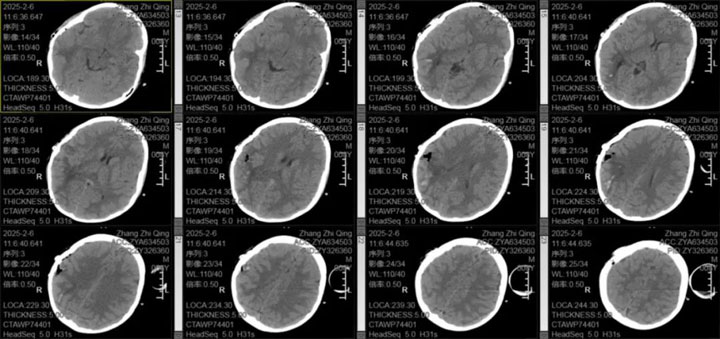

手术过程中,医生团队凭借精湛的医术和丰富的经验,不负所托,顺利完成了手术。术后,患儿未出现神经功能障碍,结果与期待完美重合,恢复情况良好。经过一段时间的精心护理和治疗,患儿最终康复出院。

此次成功救治体现了东方总院神经外科在小儿脑部疾病治疗方面的专业水平和综合实力。张德辉院长表示,每年都有颅脑损伤、脑出血的患儿行开颅手术治疗,最小年龄仅一岁,恢复良好,在治疗患儿这一方面,我们有着丰富的经验,我们将继续提升医疗技术和服务质量,为广大患者的健康保驾护航。在此,吴全主任也提醒广大家长,当孩子出现头疼、呕吐等异常症状时,务必引起重视,及时就医,以免延误病情。